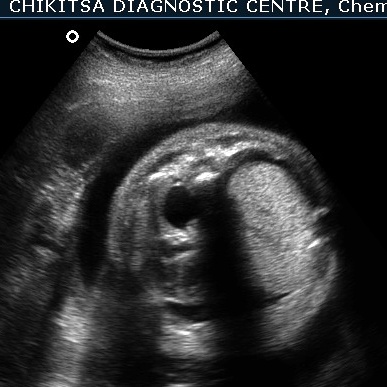

The heart is pushed to the right side, is compressed and therefore small.

There is hydrops due to cardiac failure : bilateral pleural effusion, a small amount of ascites and generalised edema in the sub-cutaneous tissue.

Since the heart and the great veins draining into the right heart (SVC and IVC) are compressed, the heart remains small in size. This reduces the venous return to the right atrium, and also the stroke volume of the heart. This is manifest as cardiac failure and consequent hydrops.